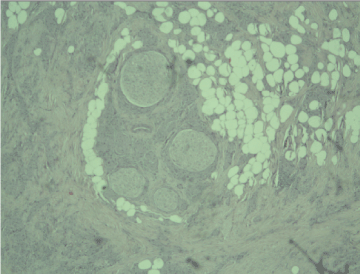

A frozen section was performed during surgery and the result was “invasive tumor, suspicious for malignancy”. Radical left mastectomy was performed with axillary lymph nodes dissection. The histological examination of the symptomatic lesion (11 mm) revealed a tumor, composed of nests of epitheloid tumor cells with monomorphous nuclei with occasional nucleoli, areas with spindle tumor cells in a fibrous background with hyaline change, areas with mature adipocytes. Peripheral nerves were surrounded by tumor nests (Figure 1). Scattered lymphocytic infiltrates were also found. PAS reaction revealed single positive granules in a few tumor cells (Figure 2). The described histological findings are observed in both mammary MFB and granular cell myoblastoma. Immunohistochemical analysis was performed. The tumor cells were positive for: S-100 protein (Figure 3), CD68 (Figure 4), Vimentin (Figure 5). The proliferative index detected with Ki67 is low (1-2%) (Figure 6). The tumor cells were negative for ER, PR and HER. The histological examination of the dissected lymph nodes revealed sinus histiocytosis, follicular hyperplasia and lipomatosis. Metastases were not found.

Figure 2. PAS reaction revealed single positive granules in a few tumor cells x40